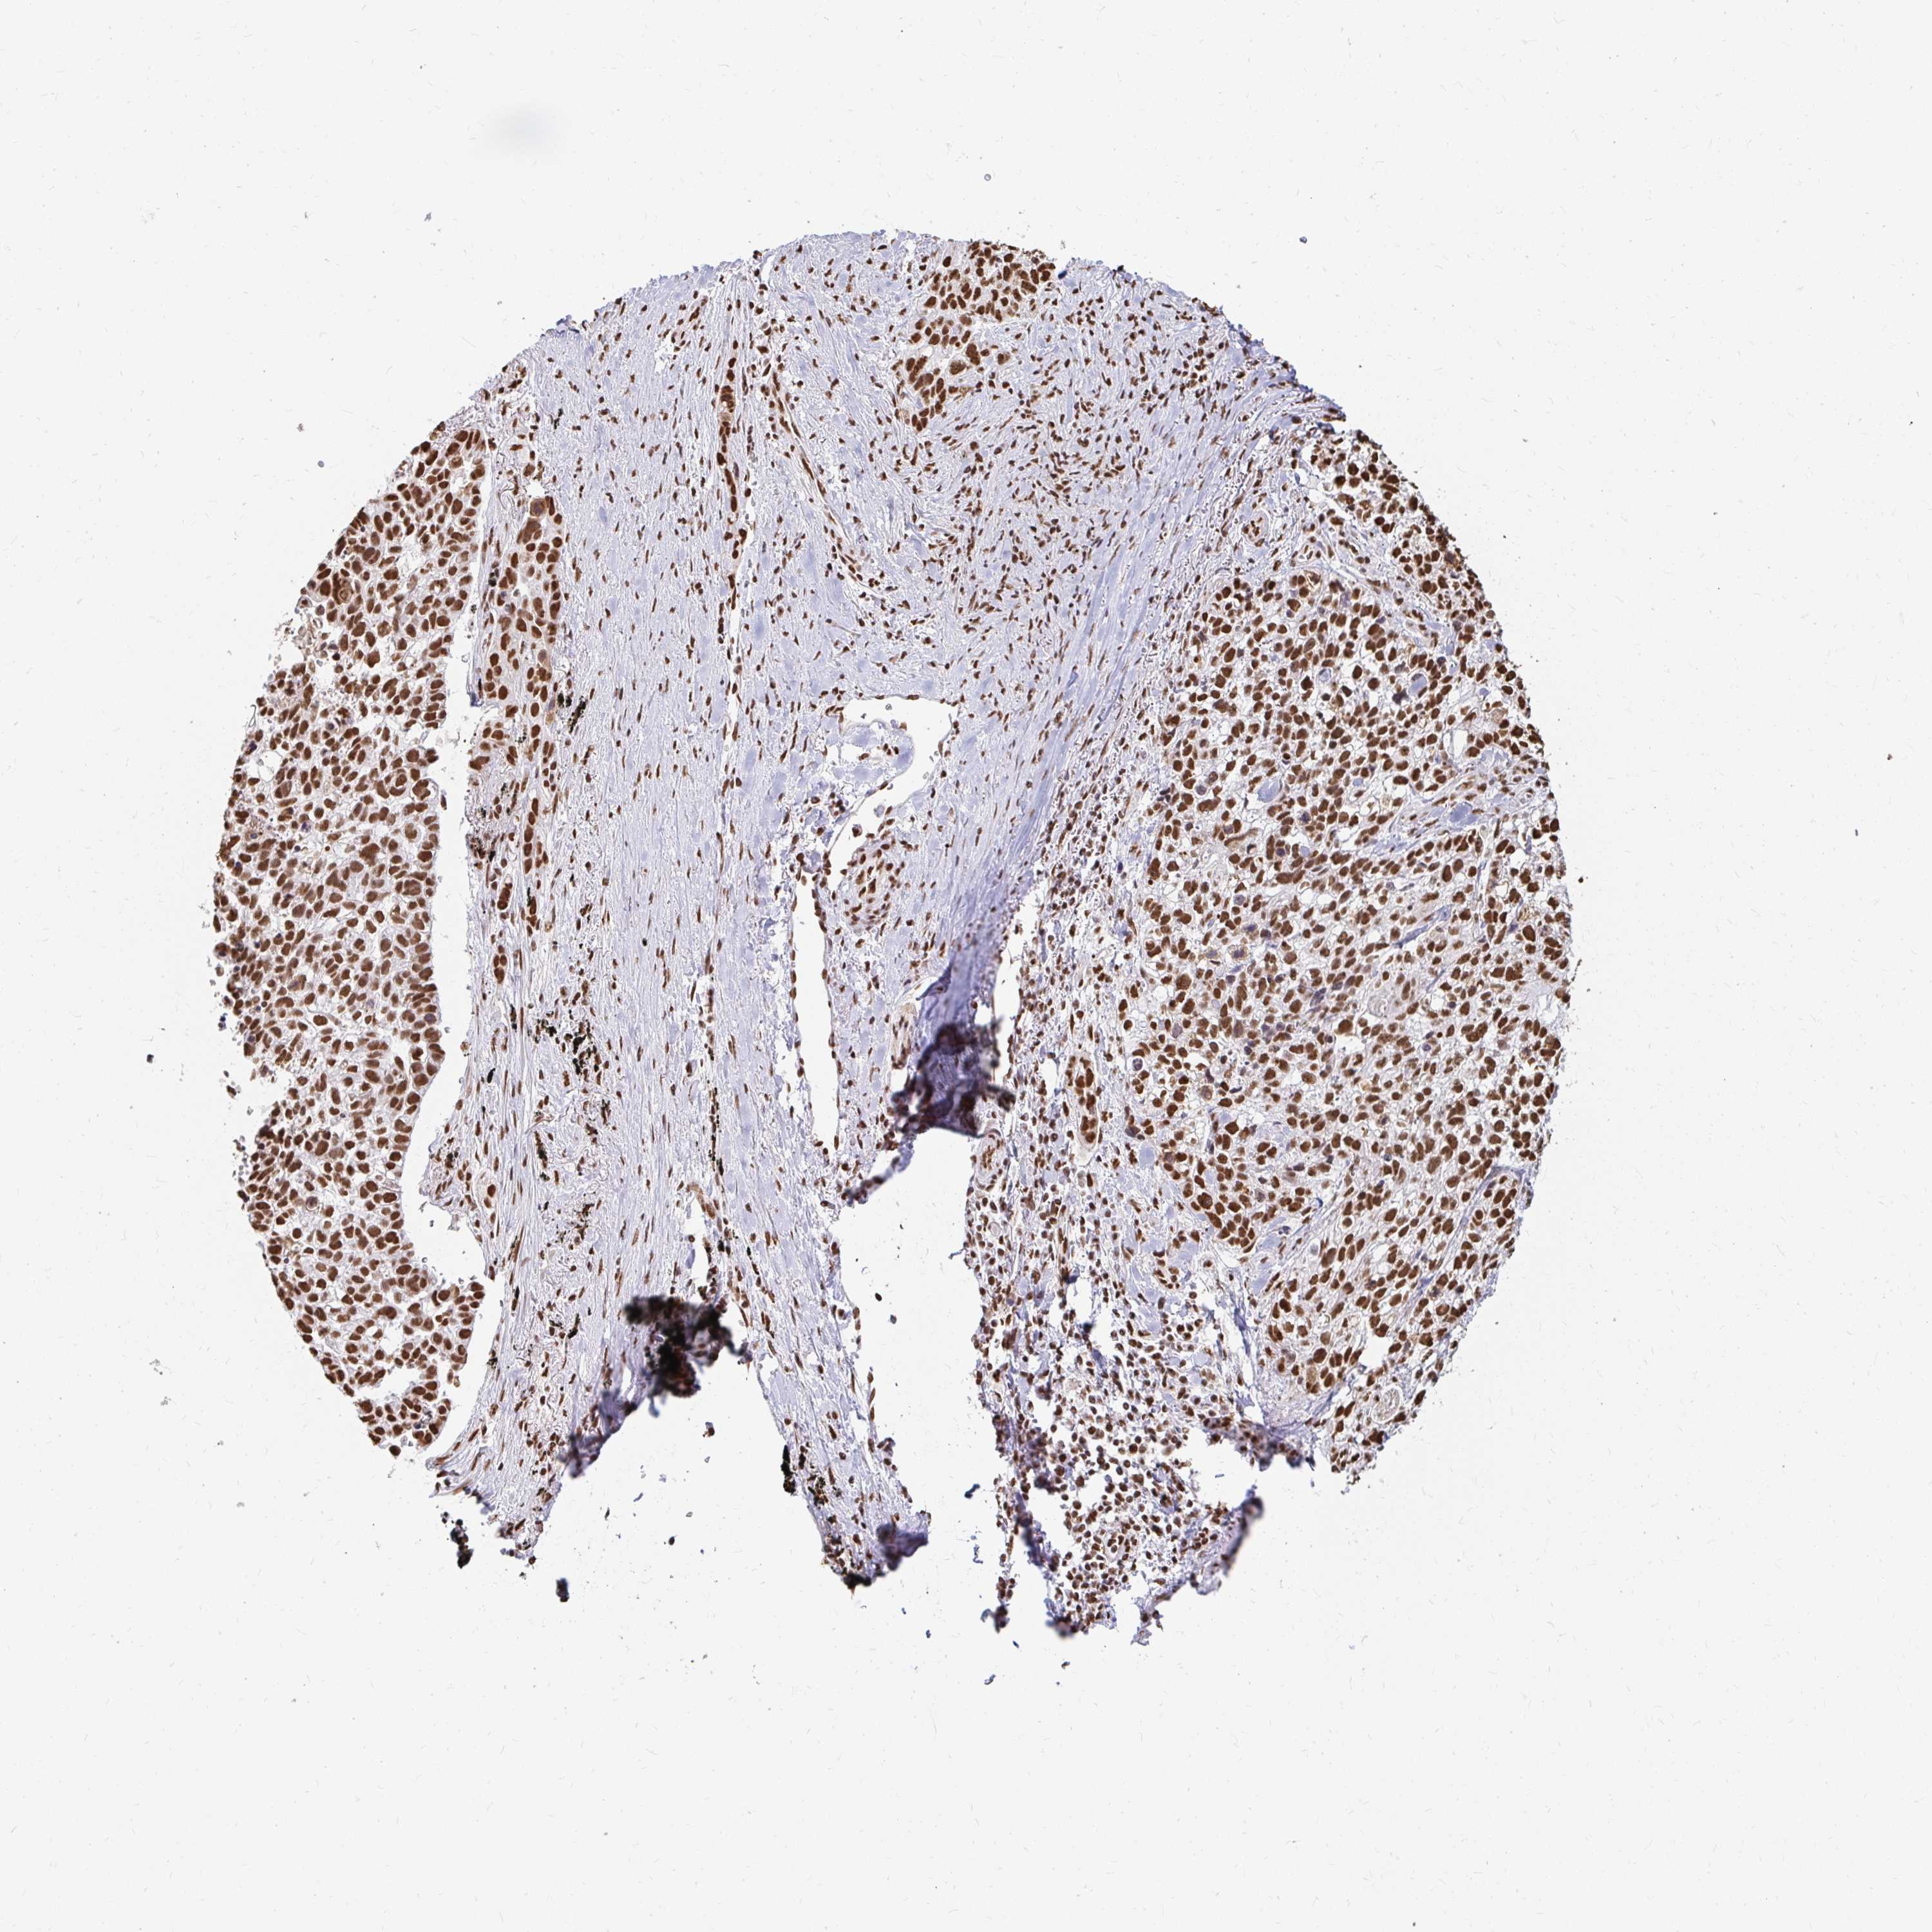

LUNG ADENOCARCINOMA (VALIDATION) - Interactive survival scatter ploti

The Survival Scatter plot shows the clinical status (i.e. dead or alive) for all individuals in the patient cohort, based on the same data that underlies the corresponding Kaplan-Meier plots. Patients that are alive at last time for follow-up are shown in blue and patients who have died during the study are shown in red.

The x-axis shows the expression levels (FPKM) of the investigated gene in the tumor tissue at the time of diagnosis. The y-axis shows the follow-up time after diagnosis (years). Both axes are complimented with kernel density curves demonstrating the data density over the axes. The top density plot shows the expression levels (FPKM) distribution among dead (red) and alive patients (blue). The right density plot shows the data density of the survived years of dead patients with high and low expression levels respectively, stratified using the cutoff indicated by the vertical dashed line through the Survival Scatter plot. This cutoff is automatically defined based on the FPKM cutoff that minimizes the p-score. The cutoff can be changed by dragging the vertical line or by entering a cutoff value in the square labeled "Current cut-off".

Under the Survival Scatter plot the p-score landscape (black curve; left axis) is shown together with dead median separation (red curve; right axis). Dead median separation is the difference in median mRNA expression between patients who have died with high and low expression, respectively. It is calculated as follows: median FPKM expression of dead patients with high expression - median FPKM expression of dead patients with low expression. This is intended to aid the user in visually exploring custom cutoffs and the associated p-scores and dead median separation.

Individual patient data is displayed and can be filtered by clicking on one or more of the category buttons on the top of the page. Categories describing expression level and patient information include: high, low, alive, dead, female, male and tumor stages. The scale of the x-axis can be toggled between linear and log-scale by clicking on the "x log" button. Mouse-over function shows TCGA ID, patient information and mRNA expression (FPKM) for each patient.

& Survival analysisi

Kaplan-Meier plots summarize results from analysis of correlation between mRNA expression level and patient survival. Patients were divided based on level of expression into one of the two groups "low" (under cut off) or "high" (over cut off). X-axis shows time for survival (years) and y-axis shows the probability of survival, where 1.0 corresponds to 100 percent.

HNRNPU is not prognostic in Lung Adenocarcinoma (validation)

Best expression cut offi

Based on the FPKM value of each gene, patients were classified into two groups and association between prognosis (survival) and gene expression (FPKM) was examined. The best expression cut-off refers the FPKM value that yields maximal difference with regard to survival between the two groups at the lowest log-rank P-value. Best expression cut-off was selected based on survival analysis .

When clicking on this number, the vertical dashed line indicating cut-off, the interactive survival plot, and the Kaplan-Meier curve will be adjusted to show results based on the best expression cut-off.

: 116.42

P scorei

Log-rank P value for Kaplan-Meier plot showing results from analysis of correlation between mRNA expression level and patient survival.

N/A

Average pTPM 150.9

Number of samples 105